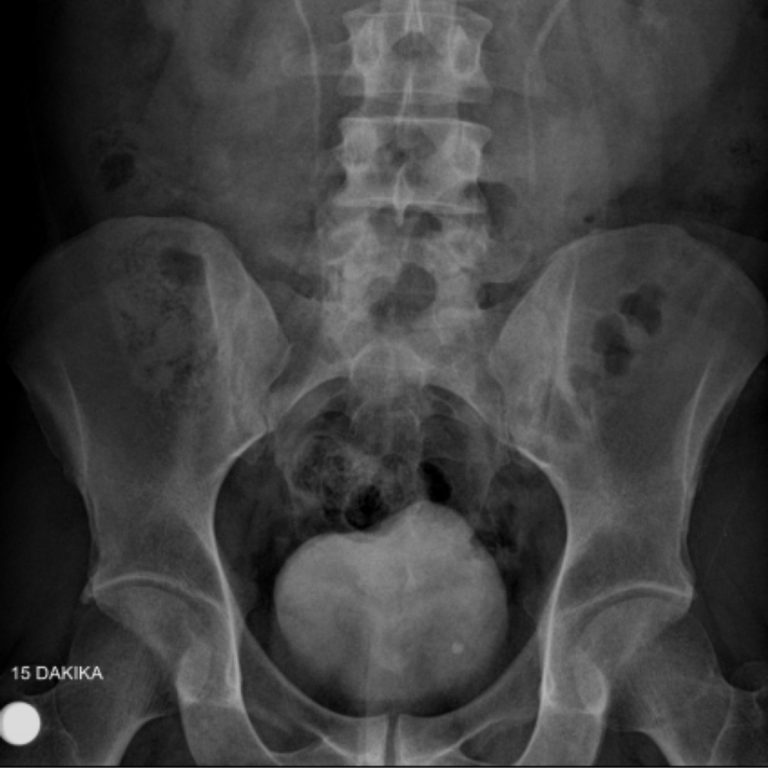

IVP- İNTRAVENÖZ PYELOGRAM

IVP böbrek inceleme filmi, böbrek ve idrar yolları hastalıklarının tanısında başvurulan radyolojik bir inceleme yöntemidir. Bu inceleme Merkezimizde,son sistem C kollu dijital röntgen cihazyla. bu alanda uzmanlık eğitimi almış hekimlerimiz tarafından yapılmaktadır.Böbrekler ve idrar yolları, karın içi organları (özellikle barsaklar) tarafından örtüldüklerinden röntgen filmlerinde net izlenemezler. Onları net olarak görüntüleyebilmek için incelemeye gelmeden önce barsaklarınızın boşaltılması amacı ile önceden “müshil” adı ile tanıdığımız bir ilaç kullanmanız gerekmektedir.Bu amaçla inceleme randevunuzdan önce size tarif edildiği şekilde hazırlığınızı yaptıktan sonra hiçbir şey yemeyerek merkezimize aç karnına gelmelisiniz.

Içecek olduğunuz müshil ilacı sizi geçici olarak ishal yaparak barsaklarınızın boşalmasını sağlayacaktır. Ilaç, etkisini genellikle 8-10 saat içinde göstereceğinden size bildirilen dozların dışına çıkmamanızı öneririz. IVP filminde; böbreklerinizin ve idrar kollarınızın görüntülenmesi amacı ile “Radyolojik Kontrast Ilaçlar” adını verdiğimiz bir ilacın damar yolu ile enjeksiyonu gerekmektedir. Bu ilaçlar “iyot” içerirler ve kana karıştıktan sonra böbrekler tarafından süzülerek, röntgen filminde böbrek ve idrar yollarının görüntülenmesini sağlarlar.

- Sol üreter distal orifis düzeyine superpoze yaklaşık 5 mm çapındaki opasite kalkül açısından anlamlı bulunmuştur. Bunun sonucu geç fazda sol üreter distal 1/3 segmenti vizualize olmuştur ve normalden hafif geniştir. Bununla birlikte sol proksimal üreter ve sol renal pelvikaliksiyel sisteminde patolojik ektazi izlenmemiştir. Bulgular parsiyel obstrüksiyona yol açan üreter orifis kalkülü açısından anlamlı bulunmuştur.

- Sol böbrek orta ve alt kaliksiyel yapılarda sırasıyla 3 mm ve 3.5 mm boyutlarında 2 adet nonobstrüktif kalkül mevcuttur.